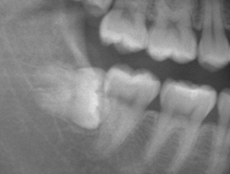

●埋伏歯(親知らず)

斜めに生えてしまったり埋まっている親知らずが痛む。また周囲の歯肉が腫れて痛い。

日本人の顎は昔に比べると小さくなってきていますので、親知らずがキレイに生えず、横に生えることや、歯ぐきに一生埋まったままのこともあります。横になって生えてくると、汚れが溜まりやすくむし歯や口臭の原因になることもあります。また、奥から歯を横に押してしまうため、歯並びを悪くする原因にもなります。